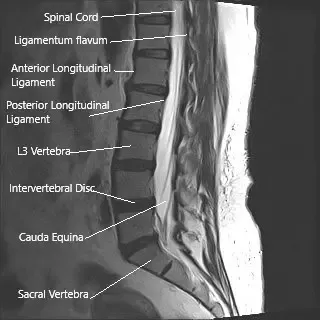

The spinal cord carries messages between the brain and the body. It runs through the spine and ends around the level of the first lumbar vertebra. Below this point, a bundle of nerves continues downward within the spinal canal—these are called the cauda equina because they resemble a horse’s tail.

These nerves control sensation and movement in the legs, bladder, bowel, and sexual organs. Because they are exposed within the canal and not protected by bone or tissue as strongly as the spinal cord, they are more sensitive to pressure or injury.

MRI of the lumbar spine in sagittal section showing cauda equina (horse’s tail)